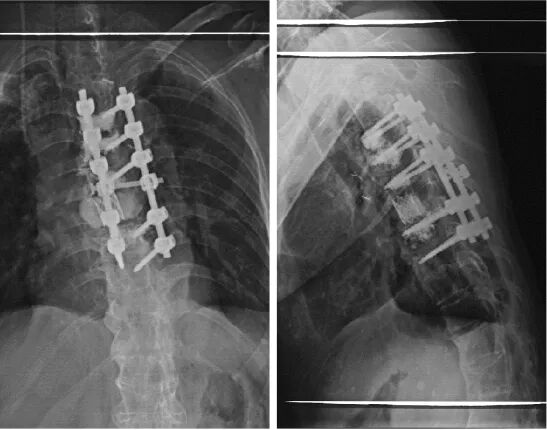

术后X线:胸7椎体切除,钛网支撑,局部填塞骨水泥;胸4-6级及胸8椎体注入骨水泥。

图4. 术后X线检查结果

患者术后自觉疼痛缓解,双下肢感觉运动明显恢复,术后2周患者下地活动。